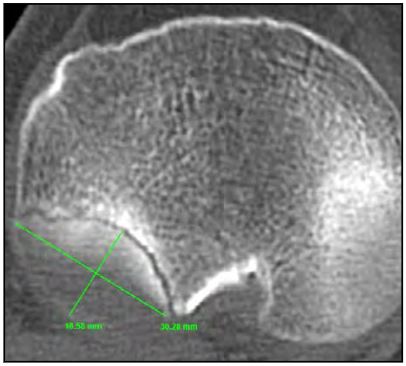

Fueron calculados el porcentaje del área de superficie articular comprometida (PASAC) del cuadrante posterolateral, (cálculo entre el área articular del platillo tibial lateral sano y lesionado); el tipo de depresión (TP) y la profundidad (PF) (distancia entre la superficie articular normal y la superficie más deprimida) o el ángulo de declinación (AD) (ángulo resultante entre una línea trazada en la superficie articular normal y otra línea en la superficie articular inclinada).

En la Tabla 2 se exponen las mediciones tomográficas de los pacientes estudiados, donde se obtuvo en promedio un PASAC 35 % (rango 20- 47 %) (Fig. 6), PF 2.50 mm (rango 1.7-3.8) y AD 29.5° (rango 24-35°) (Fig. 7).

Figura 6. PASAC: porcentaje del área de superficie articular comprometida.